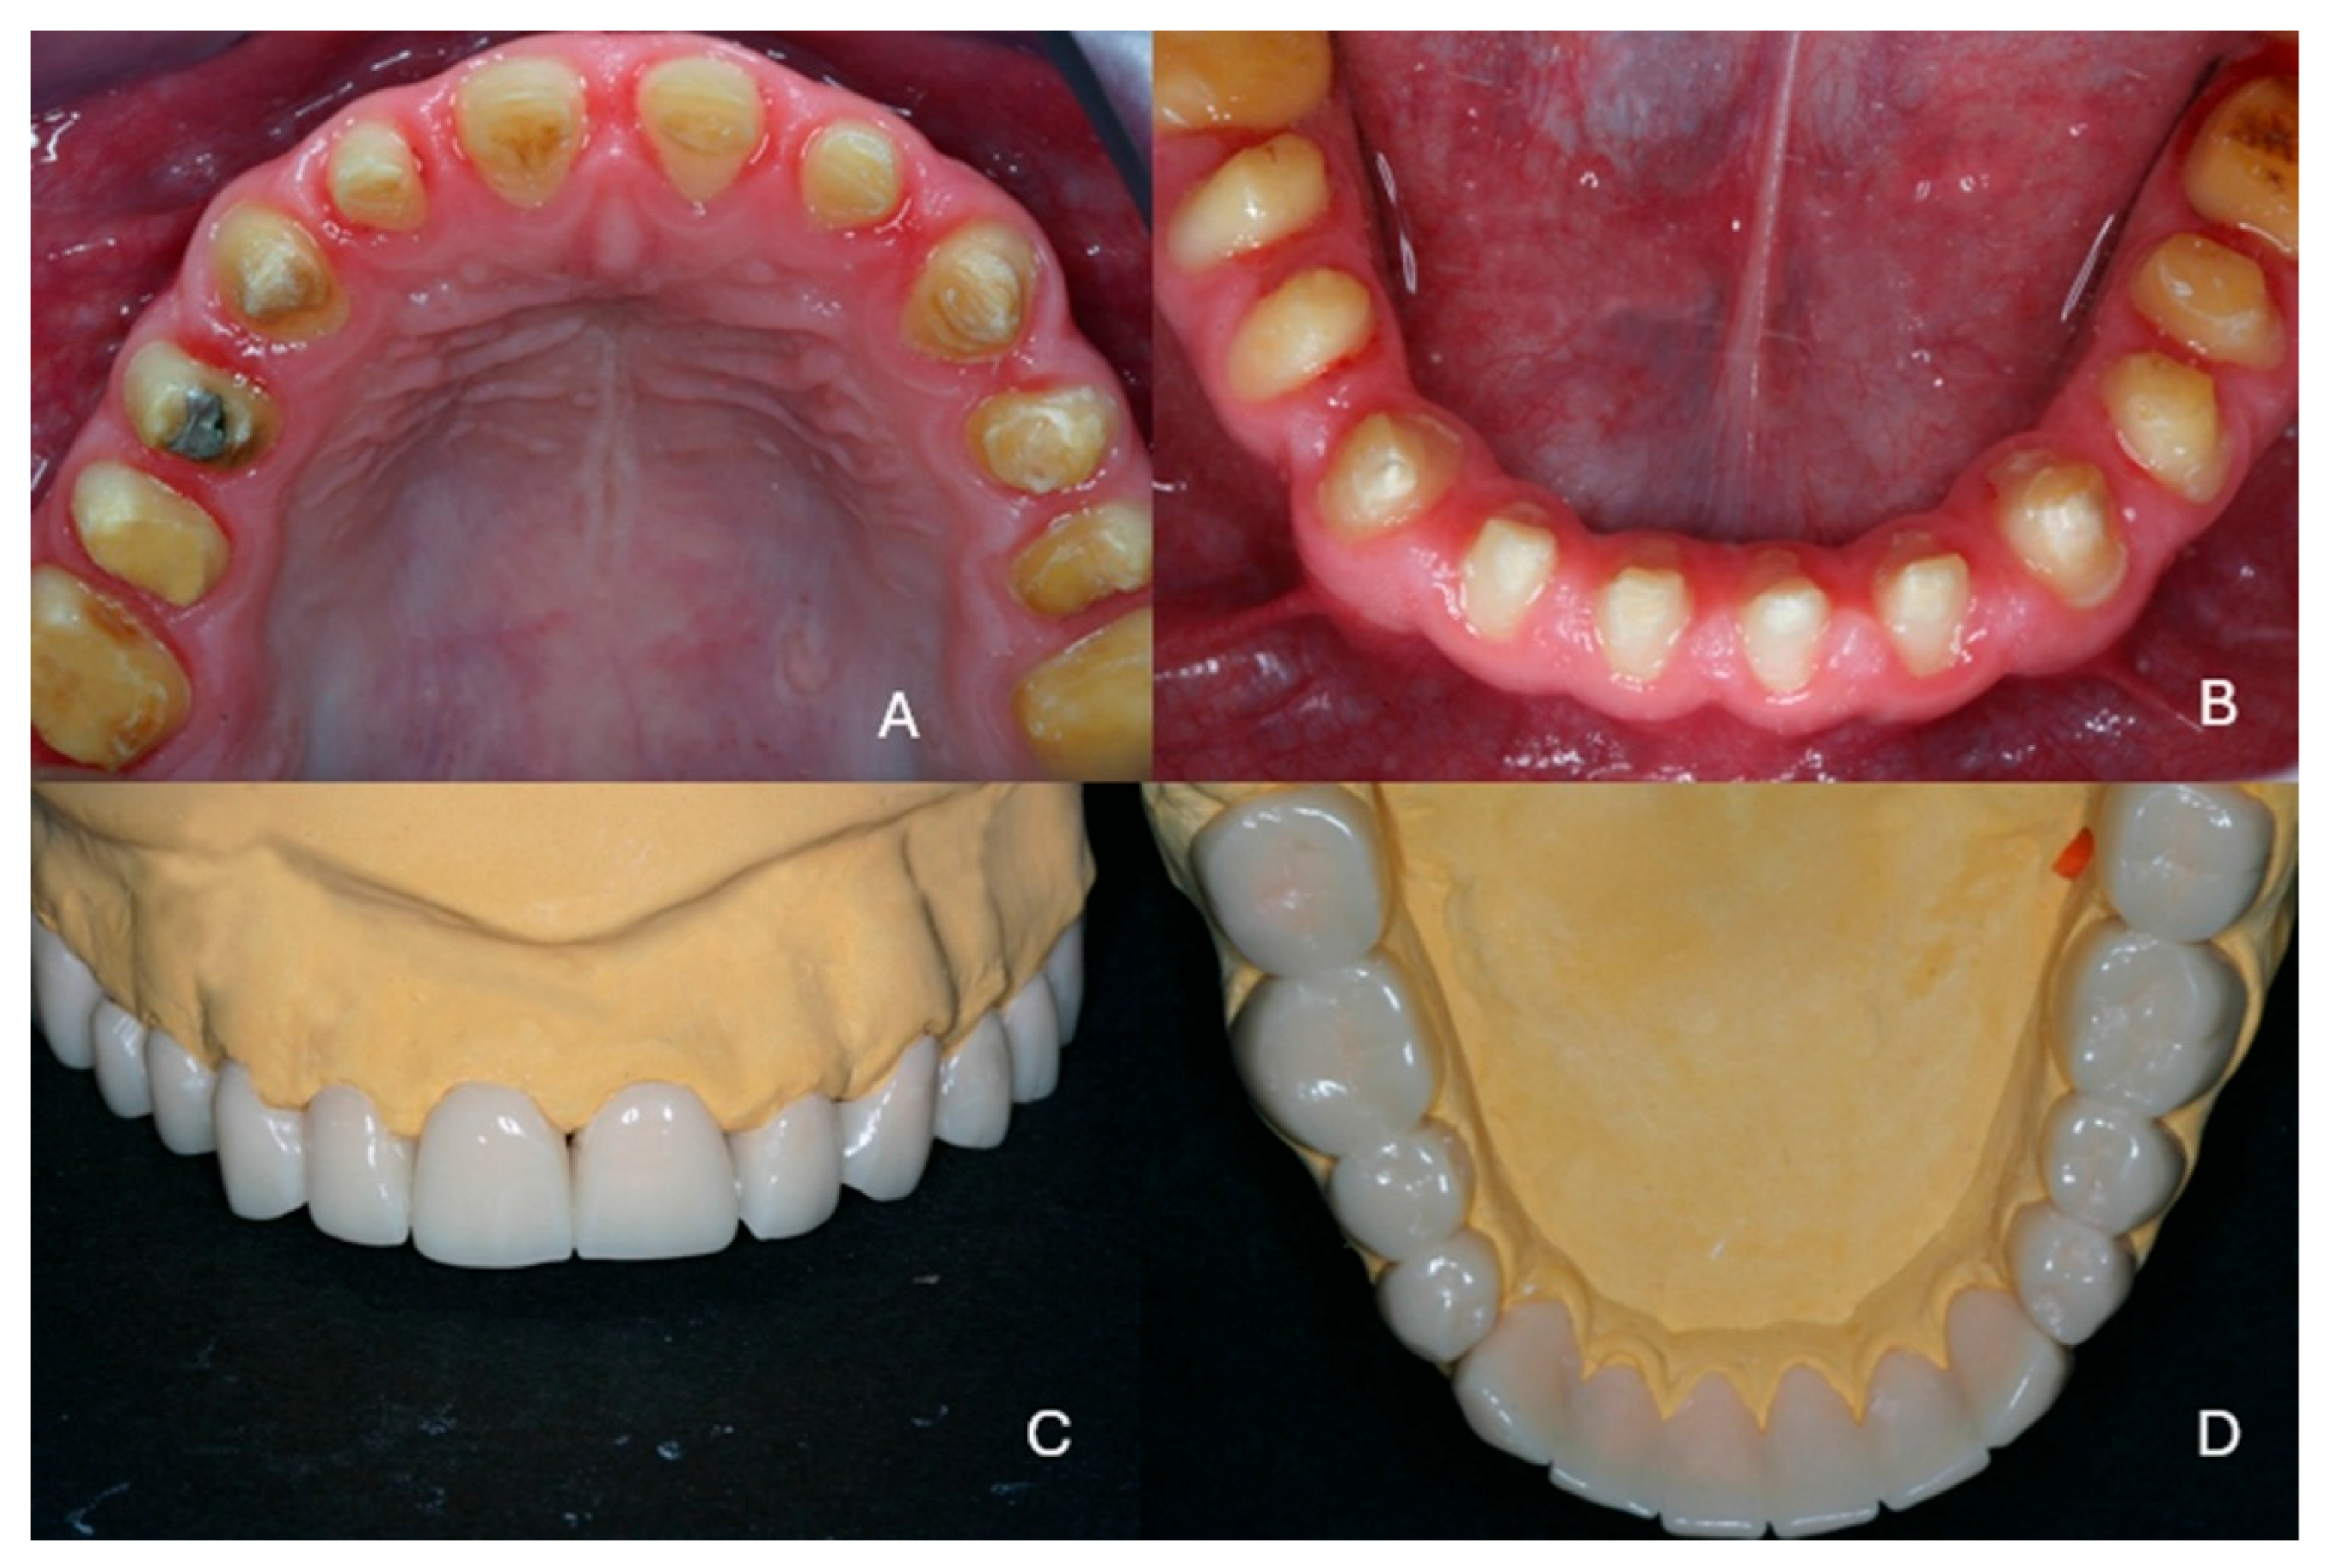

Full Mouth Rehabilitation with All-Ceramic Restorations in a Patient with Amelogenesis Imperfecta: A Case Report with 10-Year Follow-Up

2. Case Presentation